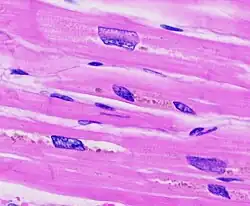

Ventricular hypertrophy (VH) is thickening of the walls of a ventricle (lower chamber) of the heart.[1] Although left ventricular hypertrophy (LVH) is more common, right ventricular hypertrophy (RVH), as well as concurrent hypertrophy of both ventricles can also occur.

The ventricles are the chambers in the heart responsible for pumping blood either to the lungs (right ventricle) or to the rest of the body (left ventricle). Ventricular hypertrophy may be divided into two categories: concentric hypertrophy and eccentric hypertrophy. These adaptations are related to how the cardiomyocyte contractile units, called sarcomeres, respond to stressors such as exercise or pathology. Concentric hypertrophy is a result of pressure overload on the heart, resulting in parallel sarcomerogenesis (addition of sarcomere units parallel to existing units). Eccentric hypertrophy is related to volume overload and leads to the addition of sarcomeres in series.[3]